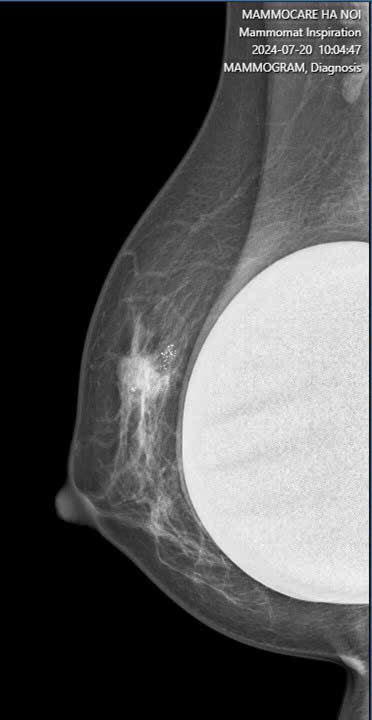

Cụ thể, kết quả X-quang cho thấy vú phải của chị có một khối nhân giảm âm với bờ tua gai trục dọc, bên trong có vôi hóa nhỏ với kích thước khoảng 12x13mm, cùng với một hạch nách phải có kích thước khoảng 13x16mm. Do kết quả nghi ngờ, chị P đã được chỉ định làm sinh thiết kim lõi và kết quả chẩn đoán là ung thư biểu mô xâm nhập, NOS, độ II, và di căn hạch nách.

Đáng chú ý, 6 tháng trước, khi chị P tiến hành đặt túi ngực, chỉ có siêu âm được thực hiện để kiểm tra. Tổn thương vi vôi hóa chỉ được phát hiện khi thực hiện chụp X-quang vú. Mặc dù tình trạng túi ngực không có gì bất thường, nhưng phát hiện ung thư vú khi được chụp X-quang đã khiến việc điều trị trở nên cần thiết và cấp bách. Hiện tại, chị P đã nhập viện K để bắt đầu điều trị ung thư.

Điều đáng nói là, khi chị P thực hiện phẫu thuật đặt túi ngực cách đây 6 tháng, chỉ có siêu âm được thực hiện để kiểm tra. Tuy nhiên, tổn thương vi vôi hóa chỉ được phát hiện khi thực hiện chụp X-quang vú. Tổn thương ung thư vú không thể được phát hiện chỉ qua siêu âm mà cần phải kết hợp với các phương pháp chẩn đoán hình ảnh khác, như X-quang vú.